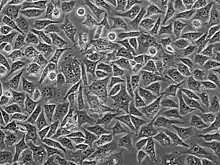

PC3 cell cultured in plastic plate